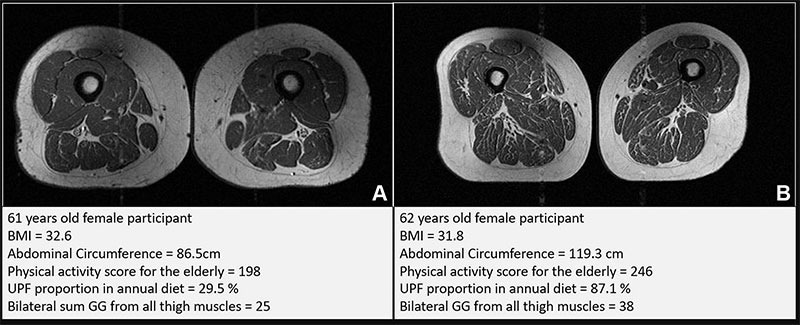

Representative axial T1-weighted spin-echo thigh MRI scans in (A) a 61-year-old female participant and (B) a 62-year-old female participant. Both participants were of similar age and body mass index (BMI, calculated as weight in kilograms divided by height in meters squared). Both had Physical Activity Scale for the Elderly scores above the mean score in the study. According to the World Health Organization definition, the participant in B qualified as having abdominal obesity (abdominal circumference ≥ 88 cm). Abdominal circumference is a measure of central obesity that captures fat distribution and serves as an indicator of cardiometabolic health. Compared with the participant in A, the participant in B had a higher proportion of ultra-processed food (UPF) in their diet (87.1% vs 29.5%) and exhibited fattier thigh muscles bilaterally, with Goutallier grade (GG) for all thigh muscles summing to 25 for the participant in A and 38 for the participant in B. Image: Credit Radiological Society of North America (RSNA)